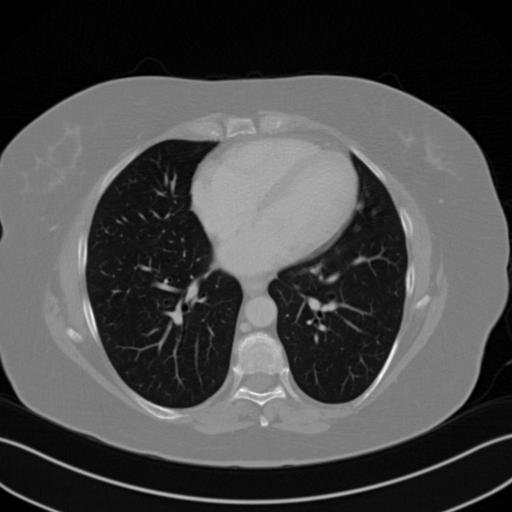

We further increase the noise level contained in the raw data to 10% white Gaussian noises and list the quantitative results in Table IV. It can be observed that the reconstruction performance of the TV model is poor in the case of high-level noises with PSNR dropping by 4 to 5 dB compared to the previous experiments. On the other hand, the performance of the learning-based methods is less sensitive to noises. The SIPID method relying on the sinogram interpolation works better than FBP-Unet. And the deep unrolling methods (i.e., PD-net, IFSR-net, SFSR-net) outperform the traditional iterative algorithm when the scanning range is limited and data is corrupted by noises. Similar to the previous experiments, compared with other deep learning algorithms, our LRIP-nets give the reconstruction results with higher PSNR and SSIM. Moreover, the low-resolution image obtained by the projection data down-sampled with rate 1/8 always gives the best reconstruction results with more than 2 dB PSNR and 0.05 SSIM increments compared to the PD-net. Fig. 6 illustrates the reconstructed images from different methodologies with scanning angular range of and 10% Gaussian noises. It can be seen that the both TV model and the FBP-Unet suffers from significant artifacts, which present distortions in the angular range of the missing scan. Other learning-based methods provides better visual qualities than FBP-Unet, and our LRIP-net1/8 still gives the best reconstruction result with correct boundaries and fine structures.

Fig. 7 manifests the reconstruction results of these methods with scanning angular of . It can be seen that both FBP and FBP-Unet produce serious artifacts within the range of missing angles. The TV model performs well in removing Poisson noises, but it can not handle the artifacts very well. Similarly, there left obvious artifacts on boundaries and different degrees of missing in visceral tissues of the reconstruction images obtained by the SIPID, PD-net and FSR-net. The visceral tissue and boundaries of our LRIP-net reconstructions are more intact and smoother, especially for the LRIP-net1/8 which gives the ideal boundaries. The observation becomes even apparent if we look at the zoom-in regions, where the LRIP-nets can produce results with fine structures. Therefore, we conclude that the low-resolution image prior can effectively improve the qualities of the limited-angle CT reconstruction.